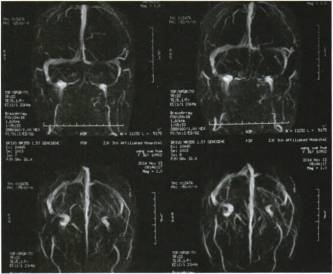

眼科检查:双眼视力0.1,矫正视力不提高。双眼角膜清,瞳孔等大,反应对称,对光反射(+),无相对性瞳孔传人障碍,玻璃体混浊不明显,双侧视水肿,隆起3PD,边界不清,周围有小片状出血及浅黄色渗出物,视网膜动脉稍细,静脉扩张迂曲,视颞侧视网膜皱褶(+),周边部视网膜未见明显异常(图1A,1B)。

图1. 双眼彩色眼底像A.右眼;B.左眼。首诊时双侧视水肿,边界不清,周围有片状出血及浅黄色渗出物,视网膜动脉稍细,静脉扩张迂曲,视颞侧网膜皱褶(+)。C.右眼;D.左眼。驱梅治疗14d后,双侧视水肿略有减轻,渗出部分吸收。E.右眼;F.左眼。6个月后,双侧视边清色正,黄斑区网膜皱褶明显减轻

给予14d驱梅治疗,青霉素240万单位静脉滴注,4次/d,苄星青霉素240万单位肌内注射,1次/周。泼尼松减至每日40 mg口服,每7 d减5 mg,逐渐减量至停药。11月28日复诊,双眼视力0.8,不能矫正。眼前节未见异常,眼底视及视网膜仍有水肿(图1C,1D)。

治疗后6个月随访时,视力0.8,矫正视力:0.8。眼前节未见异常,视边清色正,黄斑区网膜皱褶明显减轻(图lE,1F)。FFA检查:双眼视边界清晰,无荧光素渗漏(图2C,2D)。右眼视野缺损恢复,左眼视野缺损缩小(图3C,3D)。P-VEP提示双眼潜伏期和振幅正常(图4B)。血清学检查结果显示:TPPA(+),RPR(+)1:2。